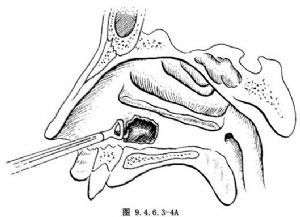

用Ostrum前向咬骨鉗咬去穿刺孔前上前下骨壁,使窗口前後約2cm,上下約1.5cm大小(圖9.4.6.3-4)。開窗後將下鼻甲復位。